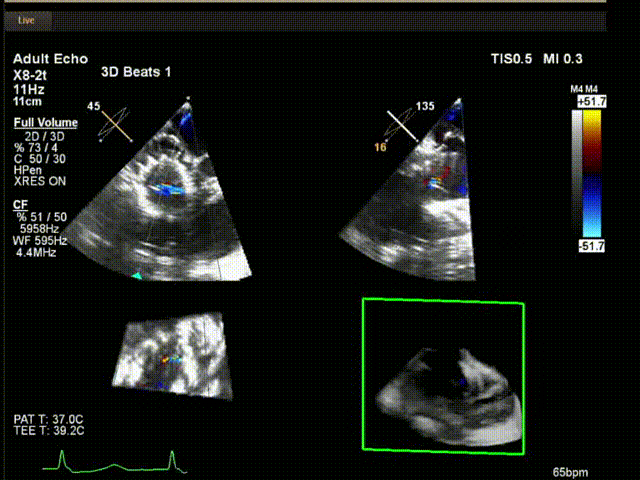

陸方林教授通過遠(yuǎn)程線上帶教的方式,與林逸賢教授團隊共同完成了此次LuX-Valve Plus人工瓣膜的首例植入。術(shù)后食道超聲提示三尖瓣反流完全消失,無瓣周漏,且LuX-Valve Plus人工瓣膜的兩個夾持鍵成功抓取瓣葉,錨定牢固,人工瓣膜穩(wěn)定性良好。